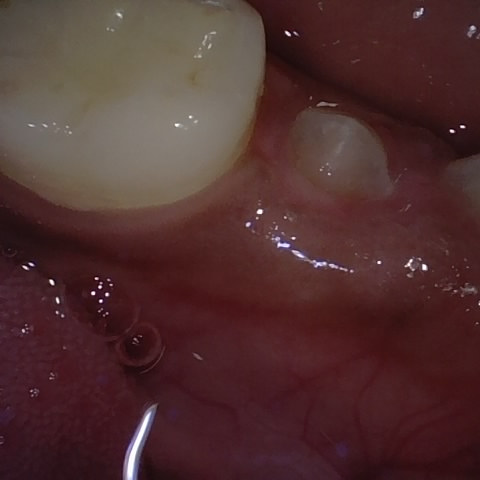

NHD25470

Annotated as "Good"